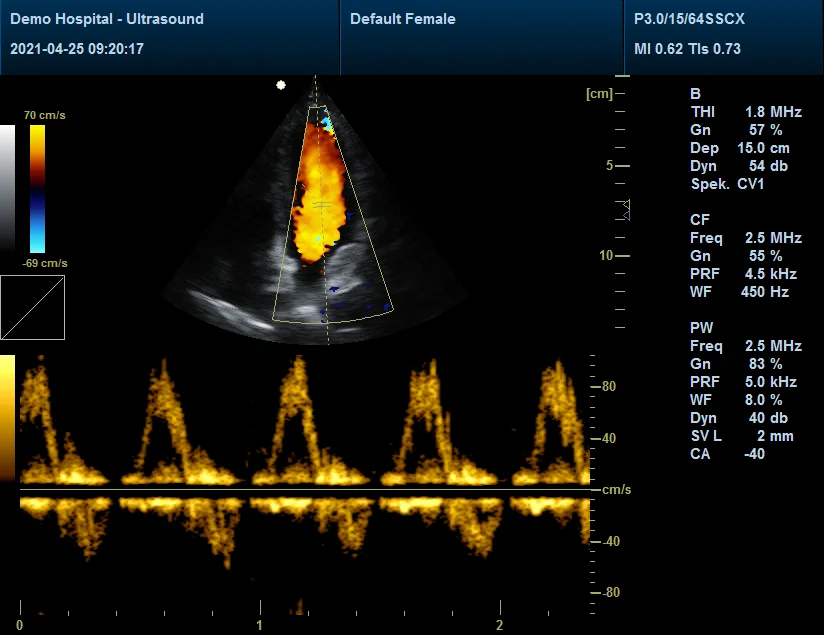

B, B/B, 4B, B/M, M

Color flow (CF), Power Doppler (PDI), Directional Power Doppler (DPDI)

Pulse Doppler (PW)

B+CF color double-frame real-time imaging

B+PW (Real Duplex),B+CF/PDI/DPDI+PW (Real Triplex)

Scanning Images